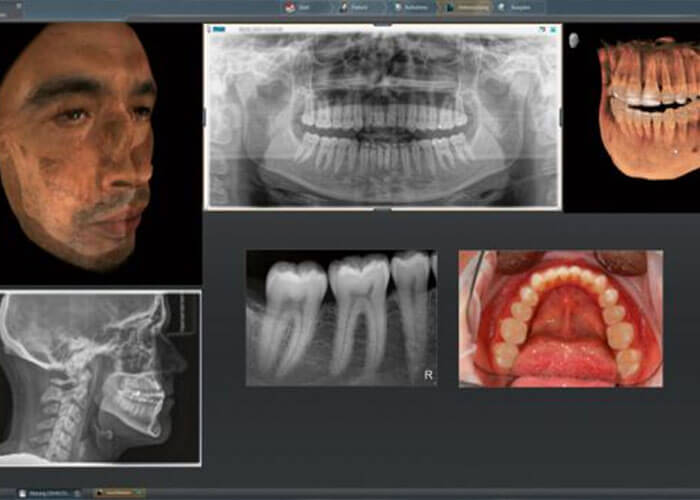

セファロ付きCT診断装置を完備

セファログラム(頭部X線規格写真)を使って、顔面、頭部のレントゲン写真を撮影して、歯や顎の骨、唇のバランスなどの計測し、噛み合わせや顎の骨のズレの検査などを行い、分析診断を実施します。矯正歯科治療で一番重要な機器は、セファログラム(頭部X線規格写真)とも言えます。なぜなら、経時的に撮影して骨格の成長の変化や歯の移動を観察しなければならいからです。

杉並区阿佐ヶ谷の歯科医院(歯医者)アート歯科クリニックでは、3D画像診断ができる高性能な機器であるセファロ対応のCT導入しておりますので、総合的な検査、そして頭部X線規格写真で精密な診断が可能です。

また、当院のCTでは、専用のソフトウェアを用いて、様々角度から患者様を診断・分析を実施致します。